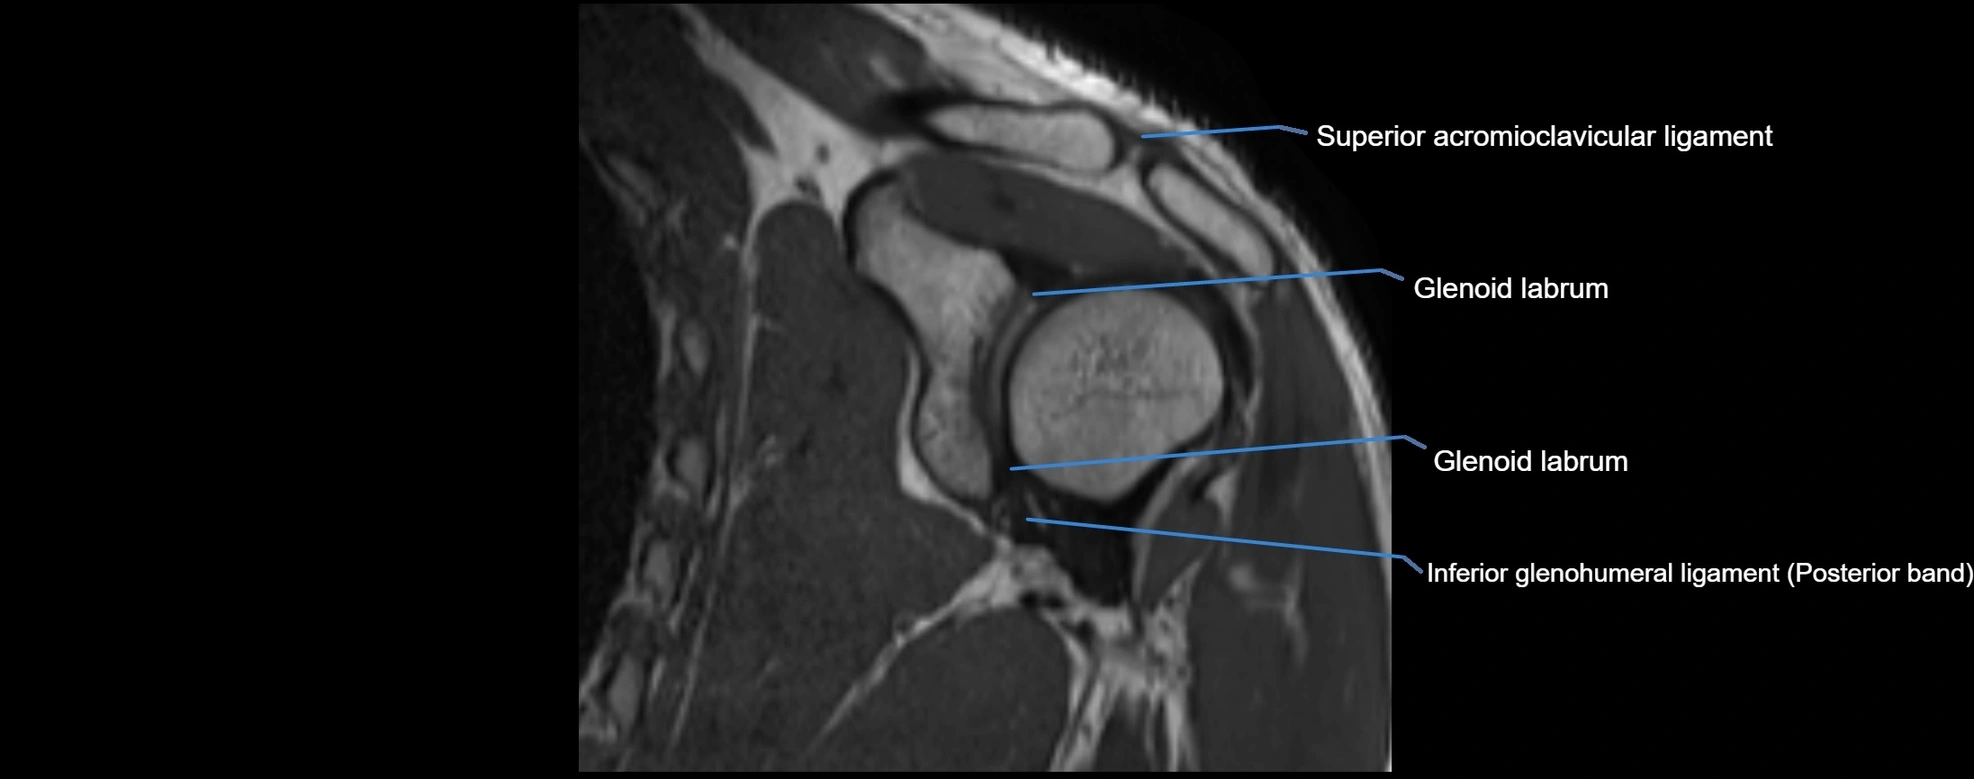

MRI images

image